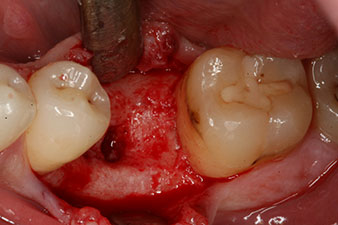

autogene Knochenspäne

Abb. 5: Für eine günstige periimplantäre Gewebekontur muss zunächst das periimplantäre Knochendefizit mit autogenen Knochenspänen ausgeglichen werden.

Dieses Modul ist für das Implantmed von W&H optional erhältlich und wird an den Implantologiemotor gedockt (vgl. Abb. 11). Der dimensionslose ISQ-Wert war direkt bei der Insertion 64 in oro-vestibulärer und 68 in mesio-distaler Richtung (Maximalwert = 100). Dies hätte eine offene Einheilung oder sogar Sofortversorgung erlaubt.

Wegen des unzureichenden Knochens krestal am Implantat wurde der Bereich mit den bei der Präparation des Implantatlagers gesammelten Knochenspänen augmentiert und speicheldicht vernäht.